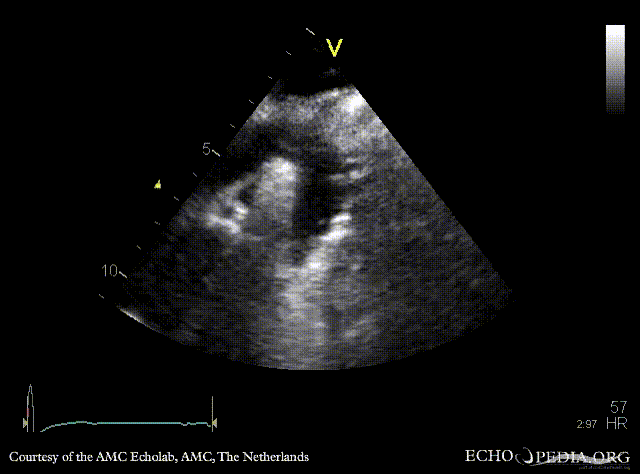

| Courtesy of: AMC Echolab, AMC, The Netherlands | |

| Suprasternal view | Suprasternal view with Color Doppler |